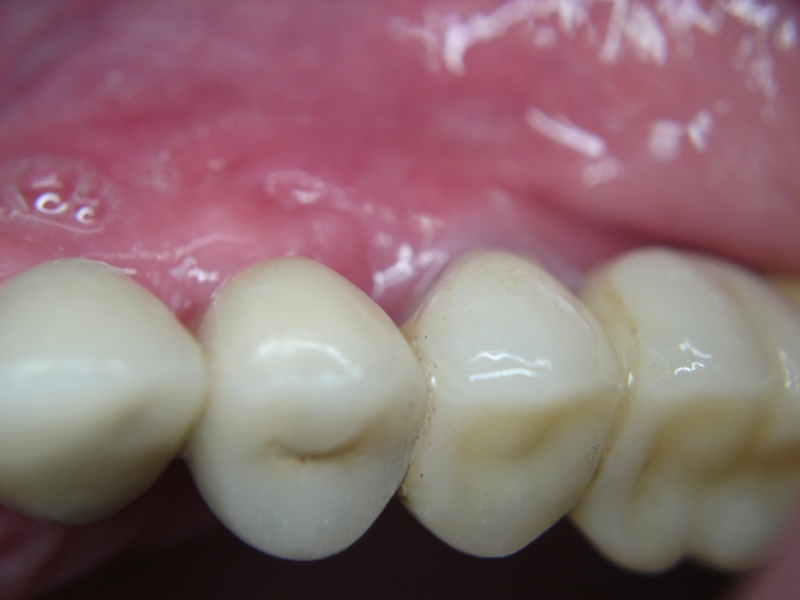

Three implants placed in a narrow posterior mandible